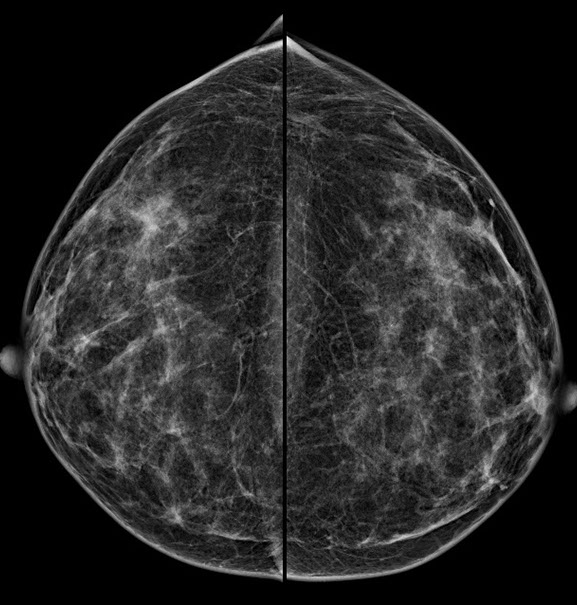

Bei der Mammographie handelt es sich um ein Röntgenverfahren, welches auf einem einfachen Prinzip beruht: Unterschiedliche Gewebestrukturen (Fettgewebe, Bindegewebe, Brustdrüsengewebe) haben eine unterschiedliche Dichte. Die bei der Mammographie verwendete weiche Strahlung wird von einzelnen Gewebekomponenten unterschiedlich absorbiert, woraus unterschiedliche Kontraste im Mammographiebild resultieren.

Mit dieser digitalen Vollfeld-Mammographie – wie sie in der Radiologie Graz St. Peter für Ihre Brustuntersuchung eingesetzt wird – ist ein entscheidender Fortschritt in der Mammographiepraxis gelungen. Die neuen Flat-Panel-Röntgendetektoren bieten eine extrem hohe Quantenausnutzung und ein hohes Auflösungsvermögen.

2.  Bessere Aussagekraft bei dichtem Brustdrüsengewebe

Vor allem junge Frauen bzw. Frauen vor der Menopause haben ein dichtes Brustdrüsengewebe. In der konventionellen Mammographie ließ sich dieses dichte Gewebe oft schlecht darstellen. Aufgrund von Fehlbelichtungen waren Wiederholungsaufnahmen notwendig, die eine zusätzliche Strahlenbelastung mit sich brachten. Die digitale Mammographie kann hingegen auch geringere Kontraste in sehr dichtem Brustdrüsengewebe deutlicher hervorheben und so eine zuverlässigere Diagnostik ermöglichen. Fehlbelichtungen wie bei der alten konventionellen Mammographie werden praktisch ausgeschlossen.

Die Diagnosesicherheit und Möglichkeit einer Brustkrebsfrüherkennung durch die Mammographie, hängt von der Dichte des Brustdrüsengewebes ab. Einteilung der Dichtegrade wurde vom American College of Radiology (ACR) übernommen.

Bei einem Dichtegrad 3 sinkt die Sensivität der Mammographie deutlich, bei Dichtegrad 4 liegt sie unter 50 %. Durch gleichzeitigen Einsatz der Ultraschalluntersuchung wird die Sicherheit in der Diagnoseerstellung jedoch wieder auf

ca. 90 % angehoben.